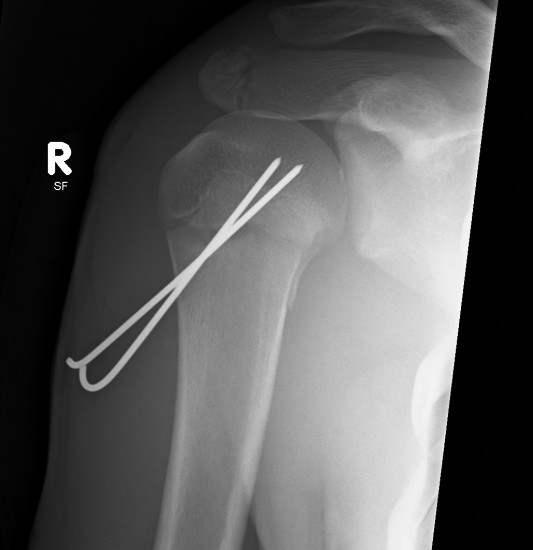

2. K wire / percutaneous pinning

Percutaneous pinning

JSJS Essential Surgical Technique

Technique

- K wires from metaphysis into head

- +/- K wire from GT down into metaphysis

- axillary nerve at risk

- begin distal

- dissect down to bone before inserting K wire